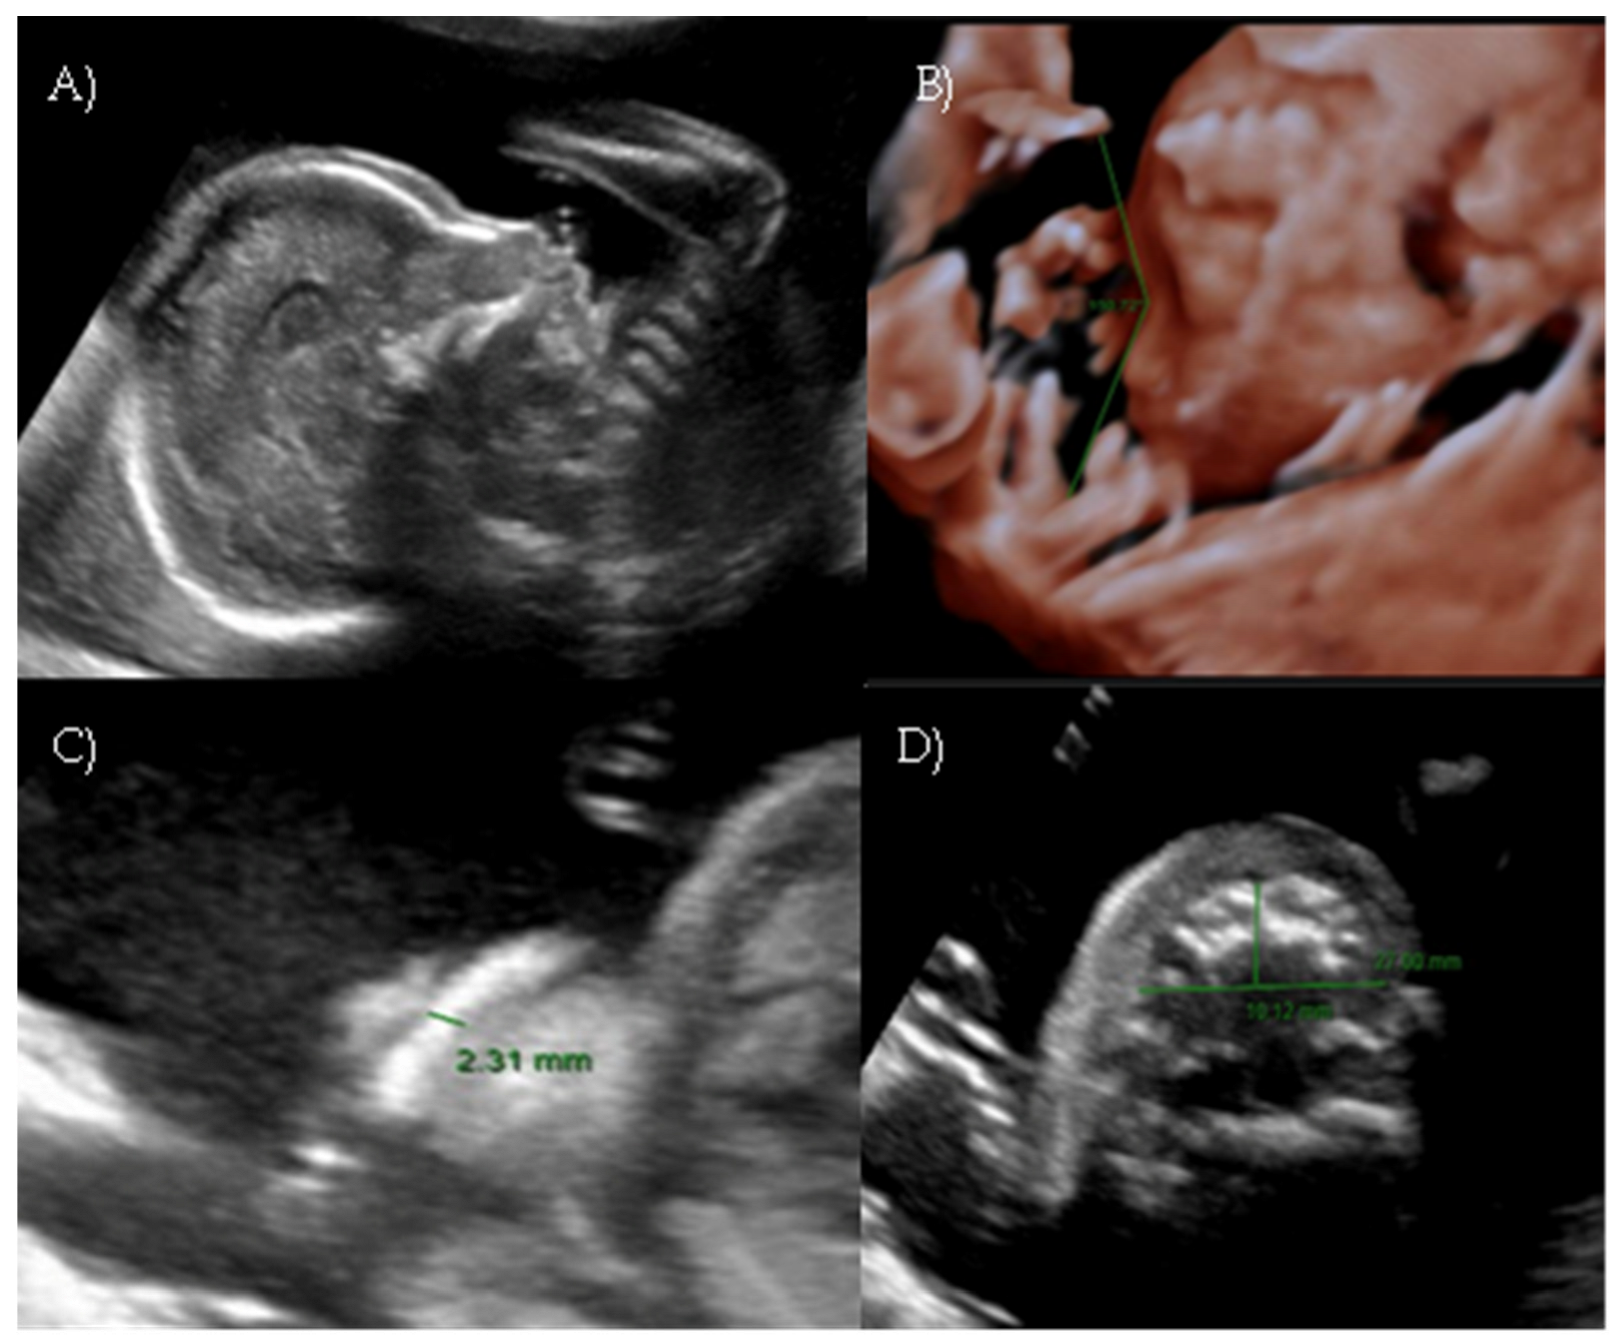

During the first-trimester scan a flat fetal profile was noted and suspected of indicating a fetal abnormality, and early re-evaluation of the fetal craniofacial anatomy was recommended (Figure 2A).

At 17 weeks and 4 days of gestation, follow-up ultrasound confirmed a flattened fetal facial profile consistent with Binder-type maxillonasal dysplasia (Figure 2B,C). Other fetal anatomy findings appeared normal.

Figure 2. Case 2. (A) First-trimester 2D ultrasound fetal profile. (B) Flat fetal profile, 3D reconstruction, at 17 + 4 w. (C) Flat fetal profile, 17 + 4 w.